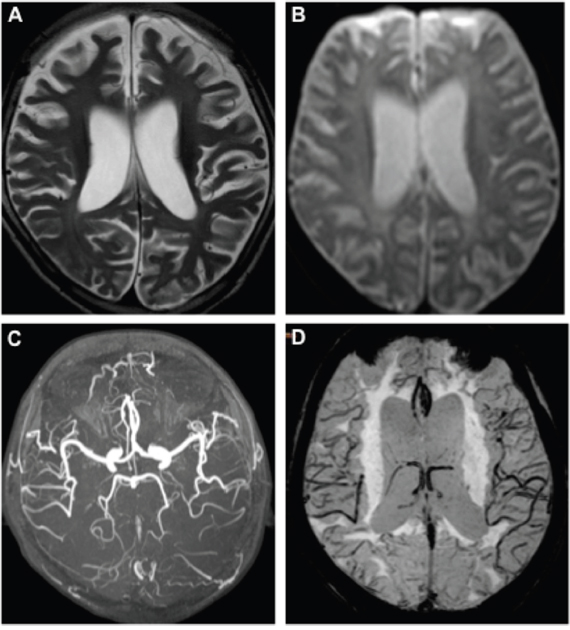

The patient’s brain MR images were showed in Figure 1. As in Figure 1A, the axial T2-weighted image indicated whole-brain atrophy and mild delayed non-progressive myelination characterized by diffuse high intensity areas in the posterior periventricular white matter. DWI (Figure 1B), MRA (Figure 1C) and SWAN (Figure 1D) revealed normal arteries and veins without ischemic or hemorrhagic lesions.

Figure 1: MR images of the RTT patient. Axial T2-weighted image (A) showed diffuse high intensity areas in the posterior periventricular white matter without obviously worsen. DWI (B), MRA (C), and SWAN (D) at age of 8 were normal.